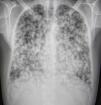

Se solicita Rx de tórax donde se objetivan múltiples nódulos pulmonares bilaterales, la mayoría cavitados (fig. 1). Dados los antecedentes del paciente y los hallazgos radiológicos la primera sospecha diagnóstica es tuberculosis, orientándose inicialmente las pruebas y el tratamiento hacia un proceso infeccioso, sin mejoría clínica.

Se completa estudio mediante TAC apreciándose innumerables nódulos pulmonares, cuyo tamaño oscila entre un tamaño milimétrico y 3,2cm, en su inmensa mayoría cavitados.